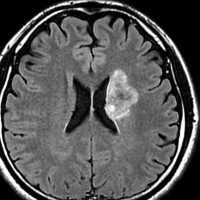

アバスチン投与後15日目

たった2週間で劇的な改善が見られました。失語症と片麻痺や認知機能も改善しました。

4回目のアバスチン投与後

アバスチンをどれだけ続ければいいのかははっきりしていません。2週間おきに6コースまでの投与が基本かもしれません。

この画像を見ると,放射線とテモダールの治療が有効であったのかなと思います。